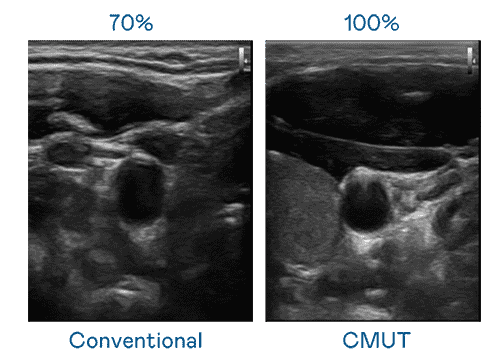

CMUT 技术是一种用电容式微机电元件来产生超音波讯号的技术。。。与传统 PZT 压电式技术相比,,CMUT 频宽增加 30%,,,,更宽频的超音波讯号让影像解析度大幅提升,,,是实现高影像品质医疗超音波扫描、、、促进精准医疗发展的关键技术。。。。

大频宽带来超清晰影像

超音波影像的解析度高低,,,,首先取决于探头能发出的讯号频宽。。森林舞会 CMUT 可提供高清晰的超音波讯号,,,提供高频宽、、高灵敏度、、、、影像纹理细节更高的超音波影像,,协助医护人员缩短影像判读时间及利用精准的医疗影像进行诊断。。。